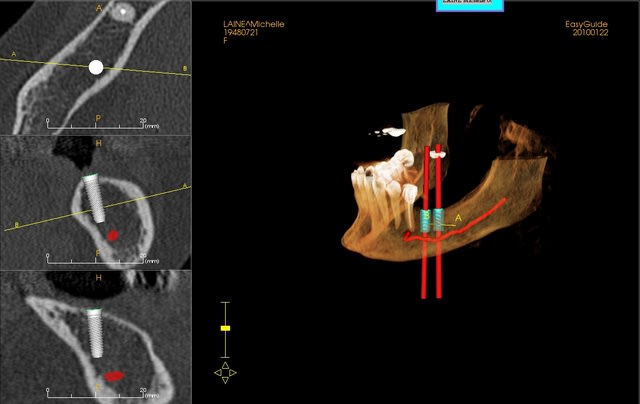

une petite étude de ton cas avec implants osseosped Astra :

12 : 3.5 x 11

13 : 3 x 11 (?)

14 : 3 x 11 (?)

15 : 3.5 x 11 (?)

16 : 4 x 11

17 : 4 x 11

je ne pratique pas donc pas de conseils sur ces implants.

Alors pour résumer j'ai fini par me lancer sur ce cas en 17 et 16 j'ai pu poser un 4*9 et un 4*8 avce l'aide des ostéotomes.

En 12 un 3,5*11 après extraction et curetage de l'alvéole.

Enfin pour ce qui est de l'expansion, merci à pxav de m'avoir fait découvrir messinger... c'est vraiment magique, même si faut pas être préssé!

saignée de 16 à 13 au disque puis àn la fraise flamme et puis passage des spreaders doucement au moteur et pour satisfaire ma curiosité j'ai aussi pu essayer les distracteurs.

J'ai eu une petite fracture de crete de 2-3 mm en 15 du coup j'ai pas osé poser sur ce site, par contre en 14 et 13 pose de 3,5*9

Mais d'après vous il n y a pas de danger à expenser (ou condenser si pres du nerf (que j ai situé là mais comme il n'y a pas de corticale c 'était super chaud à visualiser.